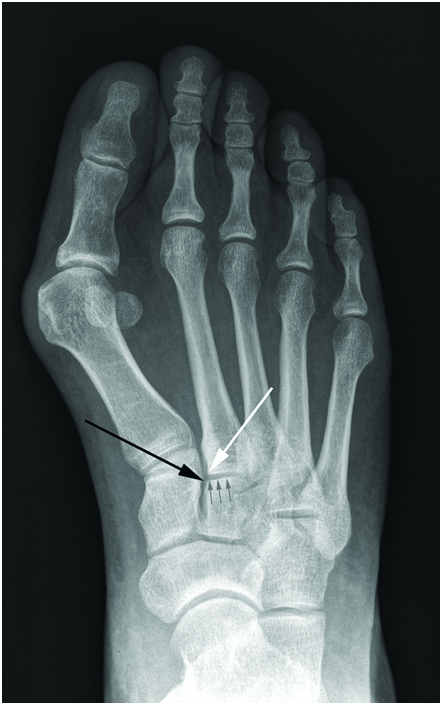

In weight bearing anteroposterior radiographs, the medial border of the second metatarsal base should be co-linear with the medial border of the intermediate cuneiform when the joint is uninjured (figure 2). In some cases, malalignment is obvious in the radiography (figure 3). Adequate anteroposterior radiographs must show a tangential view of the second tarsometatarsal joint (figure 1, right) since views oblique to the joint may miss subtle displacements (figure 1, middle). Radiographs may show a small bony avulsion type fracture between the first and second tarsometatarsal joints (figure 3, left) (Myerson et al., 1986).

Figure 2: Radiograph of a normal Lisfranc joint. The line of small grey arrows indicates the second tarsometatarsal joint line. The medial base of the second metatarsal (white arrow) and the medial aspect of the intermediate cuneiform (black arrow) line up exactly.